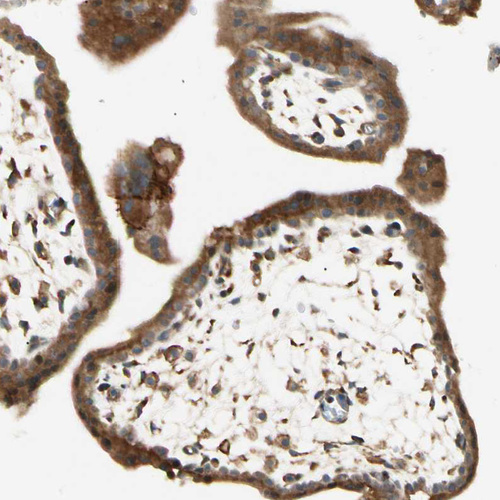

Immunohistochemical staining of human placenta shows strong cytoplasmic positivity in trophoblastic cells.